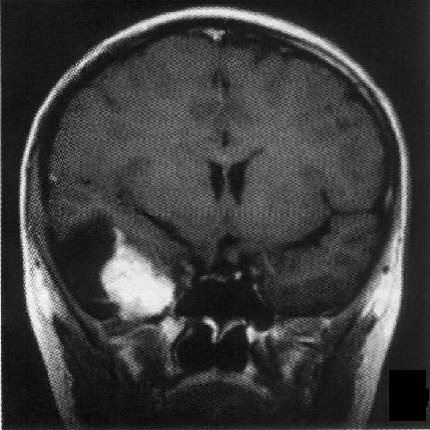

标题: PED1818:男,13岁。头痛5天,复视、呕吐3天。体检:神经生 [打印本页]

标题: PED1818:男,13岁。头痛5天,复视、呕吐3天。体检:神经生

右中颅窝见囊性占位影,其中央见块状高密度影,高密度块后后缘见条状钙化?前部与殘存颞叶皮质相连,临近骨质无异常,病灶囊变区呈长t1长t信号,实性区呈中等信号,增强(最后两副是增强t1像吧)有明显强化,实性块影上部尚见鸟嘴状影(比较像脑膜尾),考虑右中颅窝脑膜瘤可能性大,不排除室管膜瘤,畸胎瘤等

病理:囊性脑膜瘤